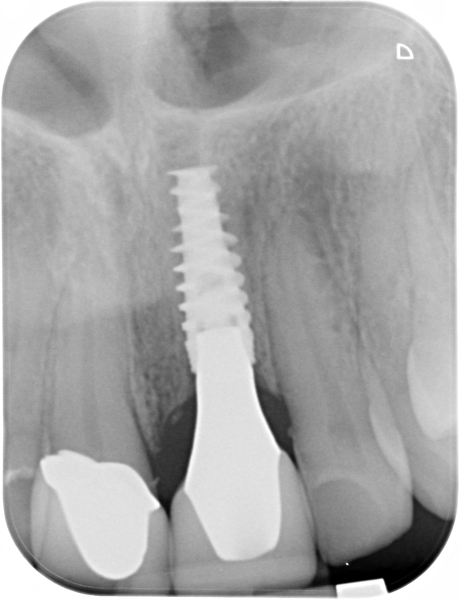

18/18 - X-ray control 15 months post-operativeGBR together with soft tissue augmentation with mucoderm® and maxresorb® - Dr. S. Scherg